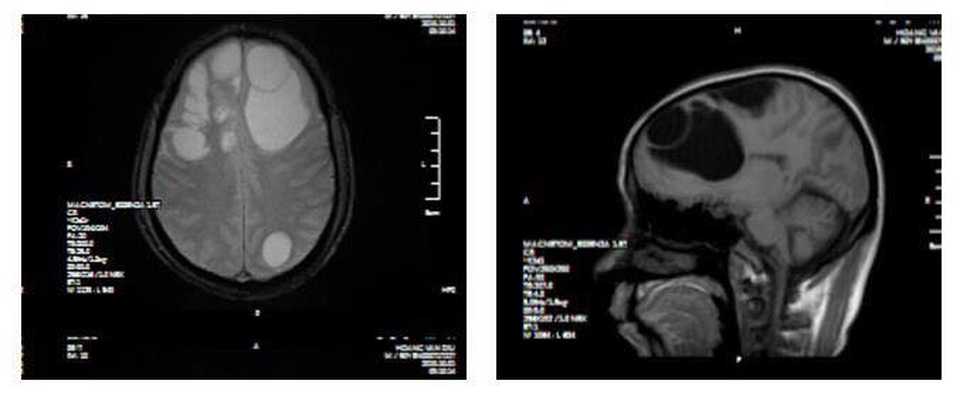

(Dân trí) - Bệnh nhân 50 tuổi (Lào Cai) được đưa vào viện với biểu hiện suy giảm trí nhớ, giảm tri giác nhanh chóng. Hình ảnh chụp CT sọ não sau đó khiến cả nhà người bệnh hãi hùng, bệnh nhân có ổ sán não khổng lồ ở cả hai bán cầu trái và phù não diện rộng.

Tại Bệnh viện đa khoa tỉnh Phú Thọ, người bệnh được chỉ định chụp CT sọ não, kết quả cho thấy ổ sán não khổng lồ ở cả hai bán cầu trái và phù não diện rộng, phải tiến hành can thiệp ngoại khoa.